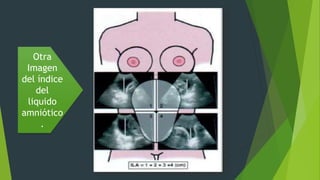

Esquema de la división del

abdomen materno en cuatro

cuadrantes, con el centro

en el ombligo.

Medida de las distancias

anteroposteriores de los

cuatro cuadrantes.

Otra

Imagen

del índice

del

liquido

amniótico

.